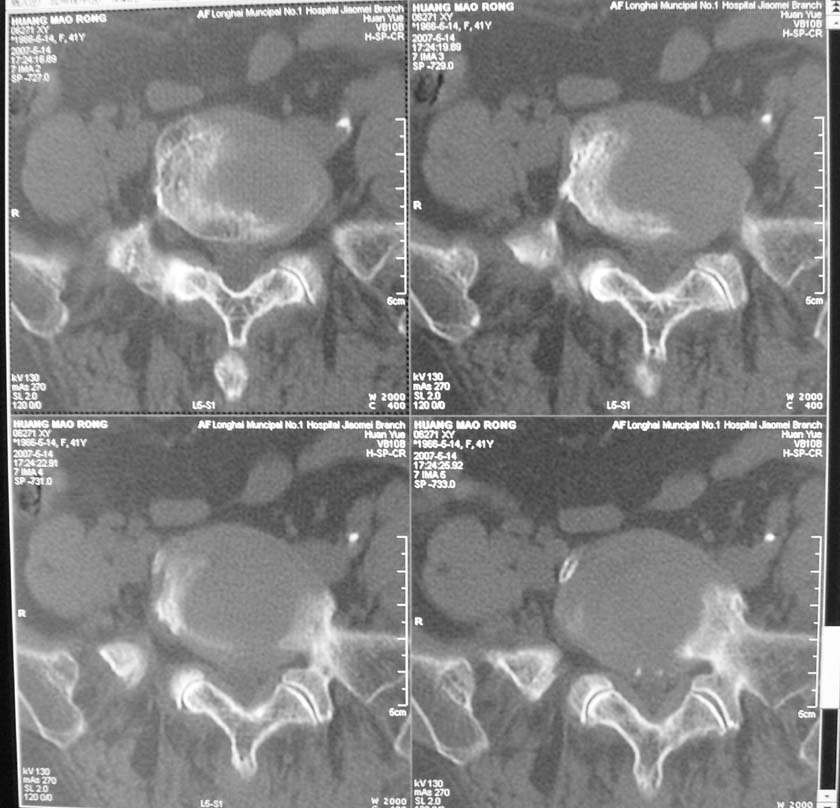

以下是引用jiangjing在2007-5-16 11:05:00的发言:[br]zhichi [br]ct所见:[br]l4-5椎间盘膨出,双侧黄韧带增厚,致使对应椎管变窄,硬膜囊受压.[br][br]l5-s1椎间盘后突,其后硬膜囊受压.l3-4椎间盘未见突出征象.[br]诸椎体边缘及对应椎小关节突骨质增生.腰椎生理曲度正常.[br]腹主动脉壁广泛钙化.[br]印象:[br]1、l4-5椎间盘膨出并双侧黄韧带肥厚及椎管狭窄。[br]2、l5-s1椎间盘突出。[br]3、腰椎及椎小关节退变。